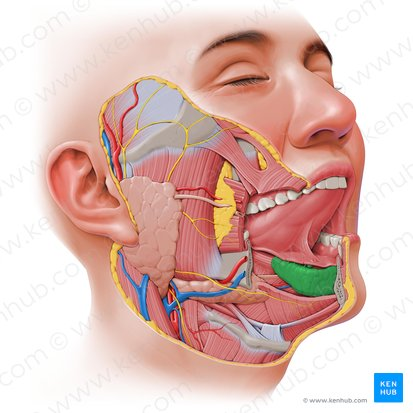

Sublingual Gland

The smallest of the major salivary glands, located beneath the tongue on the floor of the mouth. It primarily secretes a mucous-rich saliva, which contributes to lubrication.

Sublingual Duct

Several small ducts that carry saliva from the sublingual gland directly into the floor of the mouth.